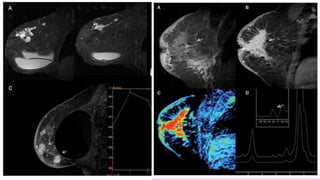

RESONANCIA MAGNÉTICA

- Estudio complementario

- S: 91-100% E: 37-67% - FP: 2.6-79.7%

TOMOSÍNTESIS

- Proyecciones Rayos X en 3D

- S: 89% E: 92%